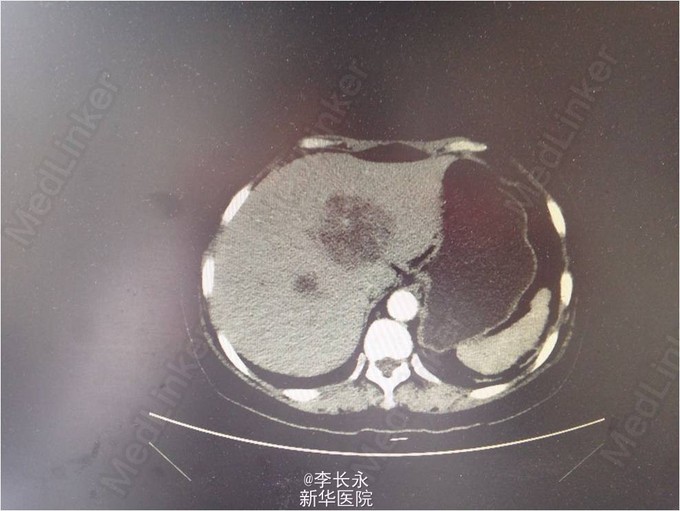

女,54岁。 患者入院前3天无明显诱因下突然出现发热,体温最高达40度,并伴有恶心呕吐,呕吐物为胃内容物,无咳嗽、腹痛腹泻等,急诊予患者抗感染、退热等治疗,患者体温恢复正常,遂回家休养,但夜间患者体温再次上升到39度。为求进一步诊治 查体:神清,气平,双瞳孔等大等圆,对光(+),HR 85次/分,律齐,未及杂音。两肺呼吸音粗,未及明显干湿罗音。腹软无压痛,肝脾肋下未及,肠鸣音正常。 辅检:CRP 106 mg/L |白细胞计数 19.00 10^9/L|中性粒细胞% 83.6 %|红细胞计数 4.52 10^12/L|血红蛋白 138 g/L|血小板计数 182.00 10^9/L 上腹部CT增强:肝内多发低密度灶,肝脓肿首先考虑,双肾小结石 诊断:肝脓肿 双肾小结石 治疗经过:予患者抗感染、保肝、调节免疫及吸氧等对症支持治疗。入院后患者诊断肝脓肿可能,故考虑行超声下穿刺,但超声科表示:“肝脓肿伴液化不全,不宜行穿刺引流置管术”,经积极抗感染治疗后,患者脓腔逐步缩小,患者体温逐步下降,无明显腹痛、腹胀,故予以出院。 随访:出院后各项生命体征平稳。 总结:肝脓肿分为三种类型,其中细菌性肝脓肿常为多种细菌所致的混合感染,约为80%,未穿刺不能明确诊断,对症处理,定期随访